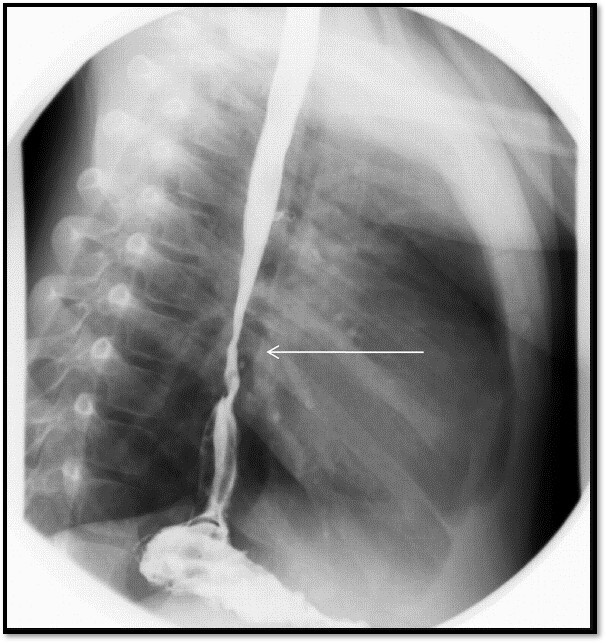

What pathology is shown here?

Esophageal Atresia